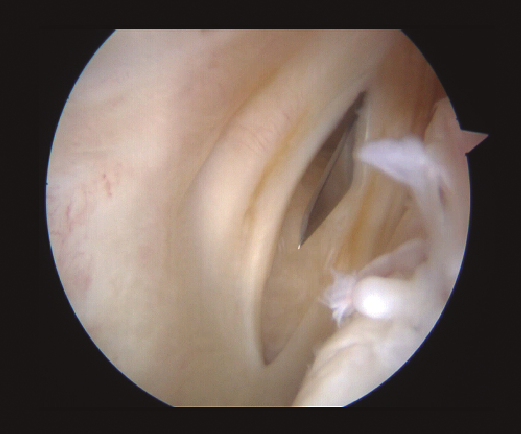

Aunque no se aprecien signos de inestabilidad meniscal desde una visión anterior, se realiza de forma sistemática una exploración del segmento posterior. Se realiza sistemáticamente una exploración visual del compartimento PM a través de la escotadura intercondílea, con flexión de rodilla de 90°. El artroscopio es introducido por el portal AL en el triángulo formado por el cóndilo medial, el ligamento cruzado posterior y la espina tibial. Tras introducir el artroscopio en este espacio, podemos avanzarlo hacia posterior sobre el borde del cóndilo, realizando un valgo forzado primero en flexión y luego en extensión. La rotación interna de la tibia puede ayudarnos en la visualización. Este gesto subluxa el platillo tibial posterior y produce una traslación posterior del tercio medio del platillo tibial. Con esta maniobra se pueden visualizar dos tercios de las lesiones periféricas que vayan desde el segmento posterior hasta el segmento medio. En caso de desgarros del segmento posterior, se realiza un portal PM (Figura 2). Mediante transluminación, el cirujano puede observar las estructuras vasculares y nerviosas de la zona para realizar el portal con seguridad. El punto de introducción de la aguja se sitúa proximal a los isquiotibiales, 1 cm posterior a la interlínea articular femorotibial medial. La rodilla se flexiona a 90° para evitar daños en el paquete poplíteo. La aguja se introduce de fuera a dentro en la dirección de la lesión.

Figura 2. Visión artroscópica a través del intercóndilo de la creación del portal posteromedial.